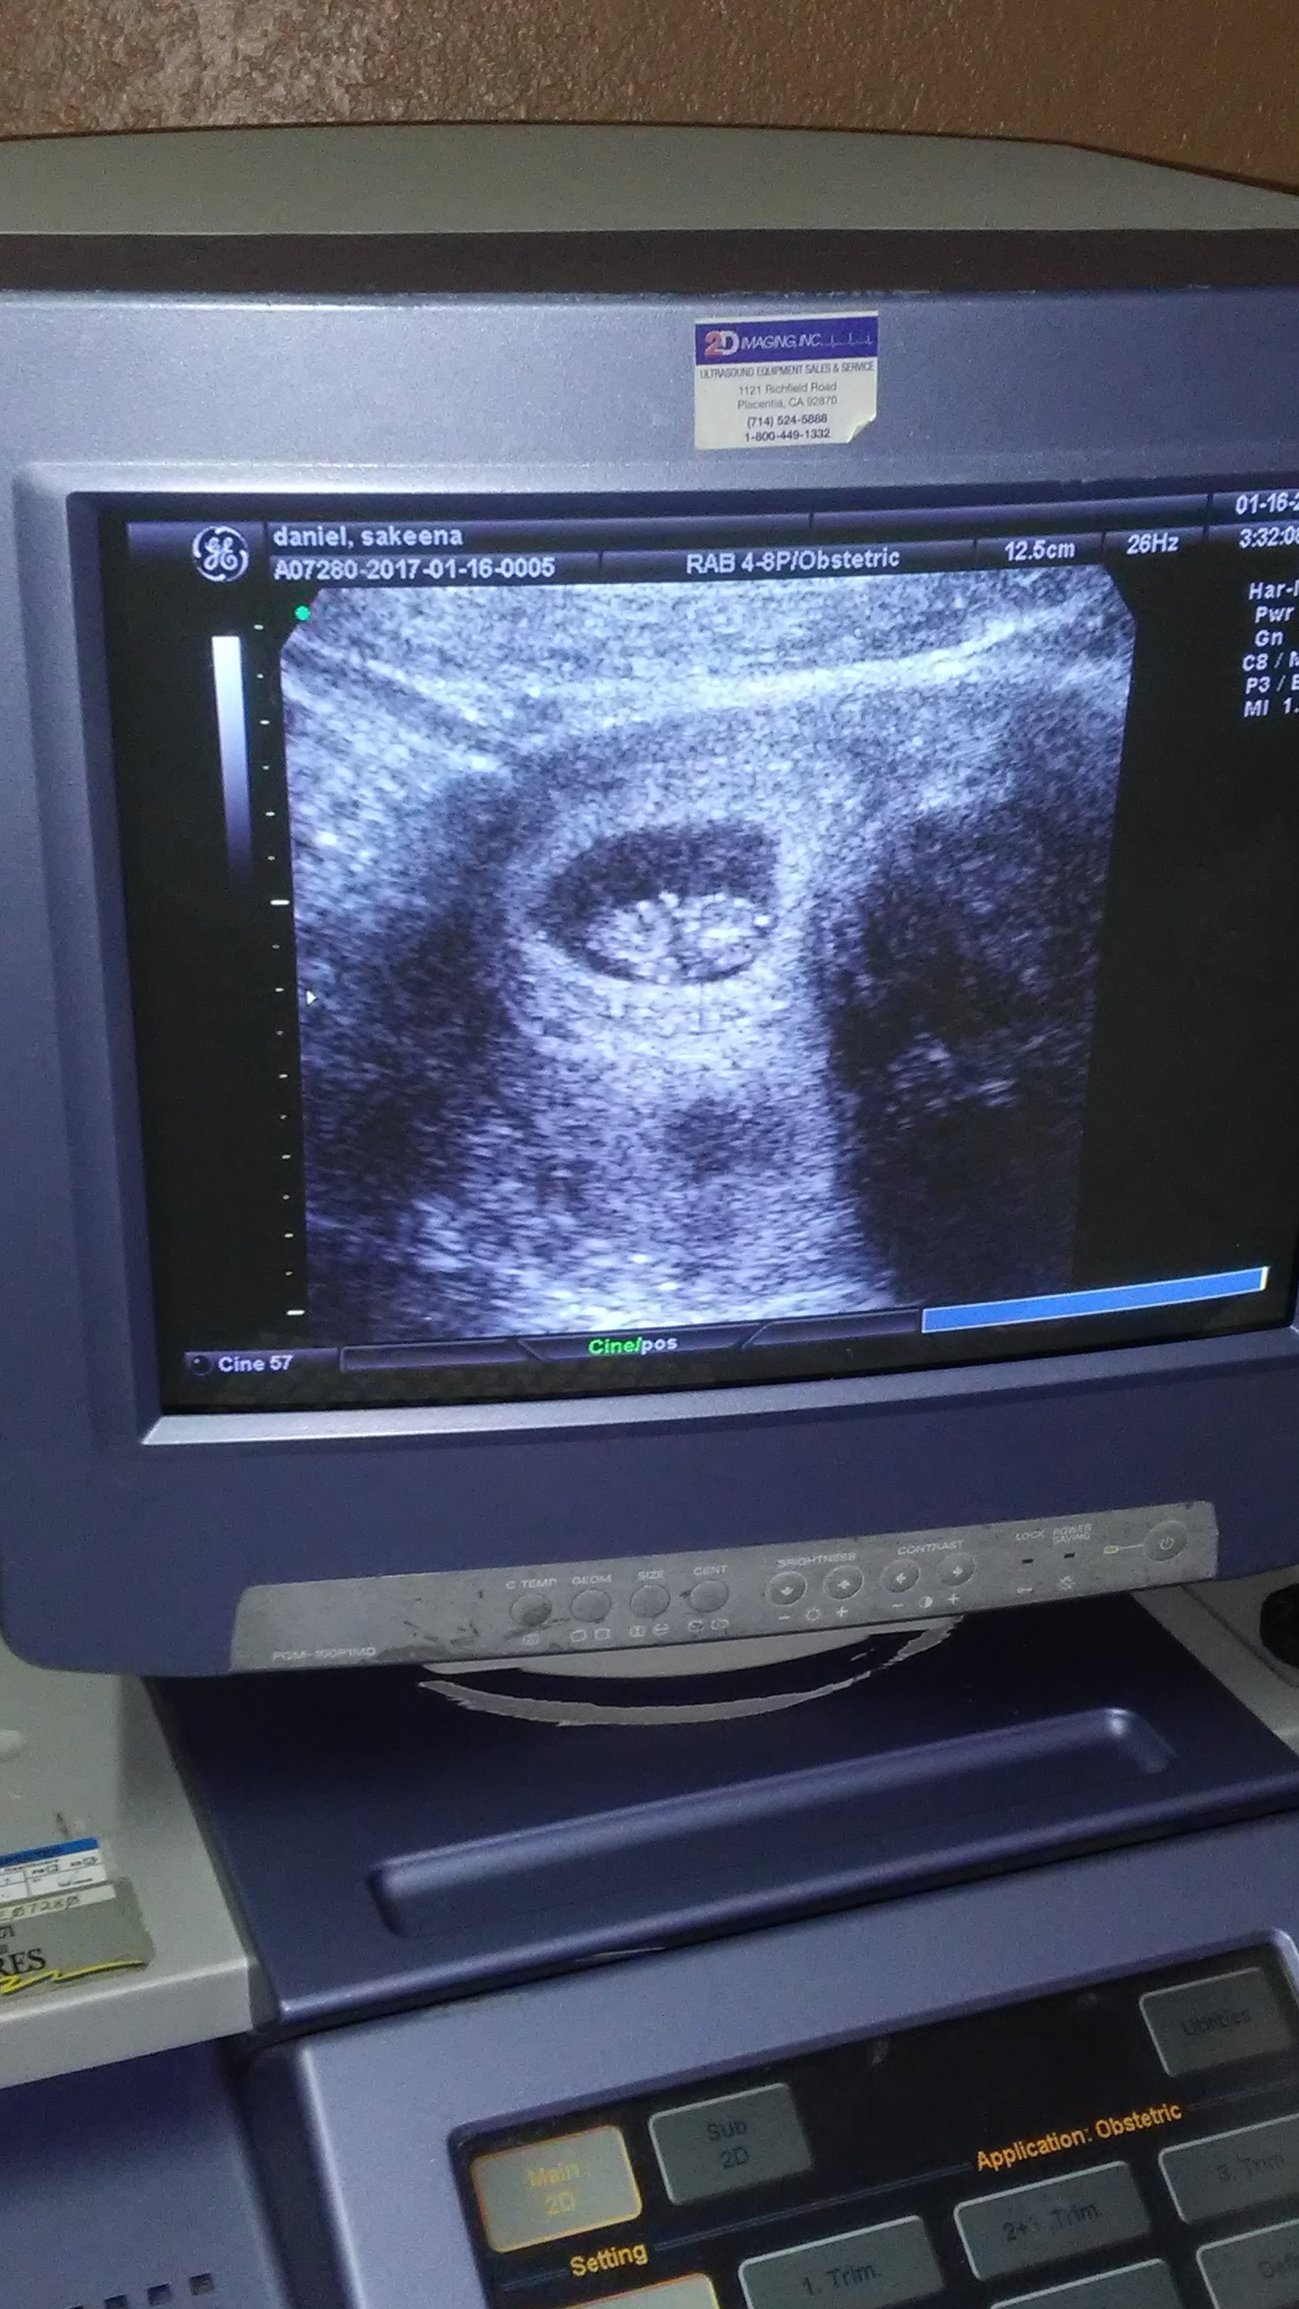

Thanks for asking @HGRich, it was a horrible experience. The OB was very unprofessional and insensitive. As soon  soon inserted the camera she said there is nothing there. I was shocked! "Could you look around  give it  sec?" Nothing was shown except the sac. She immediately offered me the abortion pill to get rid of "it" quickly. I was stunned. No compassion whatsoever, no explanation of what could be wrong, nothing! Once I refused the pill she proceeded to tell me I will abort within the next couple of days  no follow up was necessary! I am not joking nor exaggerating. I hurried up got dressed and got out of there. My boyfriend was still sitting there in shock!

Devastated at first then anger took over! I was encouraged to get a 2nd opinion.... I have not had any bleeding, cramping, or extreme pain. I still feel pregnant. Boobs are very sore, peeing all day, and cravings. I'm standing on faith until I see different. I filed a grievance with my insurance and requested a different OB who comes highly recommended. I have an appointment for Feb 7th by then I will just be hitting the 2nd trimester. I'm still taking my prenatal vitamins, praying for, and talking to my baby. If she was correct I will accept it but not from her. She is in the wrong business.

I will keep you posted. Please keep me in your prayers and thoughts.

• @keenad76 I'm so sorry. I will definitely be praying for you. It's weird that you have to wait so long until the next appointment. Is there any way you could pay for a "vanity" ultrasound at an imaging center? They're not allowed to tell you if there's something wrong, but it would be another chance to see. Alternately maybe you could try a crisis pregnancy center. A Christian or catholic one would NOT push any decisions on you and help you out a bit. I don't know what to think about the fact that they couldn't find anything, but as long as you're not showing signs of loss, hang in there. Thinking of you.

• @keenad76 that's wonderful! I'm so glad you wanted to get that baby a second opinion! I still can't believe that other clinic was so rude to you but I'm so glad this new one helped you and let you see that little bean! Will be praying for you and that little one and your boyfriend in the weeks ahead. Thanks for updating us!

• @keenad76 OMG that's awesome awesome news! Congratulations!!!!

• @keenad76 yay! Looks great! How far along did they say baby was?